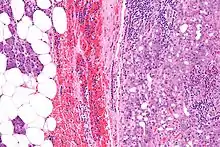

| Micrograph of an acinic cell carcinoma (right of image) and acinar glands (parotid gland - left of image). H&E stain. | |

Basophilic, bland cells similar to acinar cells. Growth pattern: solid - acinar cells, microcytic - small cystic spaces mucinous or eosinophilic, papillary-cystic - large cystic lined by epithelium, follicular - similar to thyroid tissue.

These tumors, which resemble serous acinar cells, vary in their behavior from locally aggressive to blatantly malignant.

Intermed. mag.